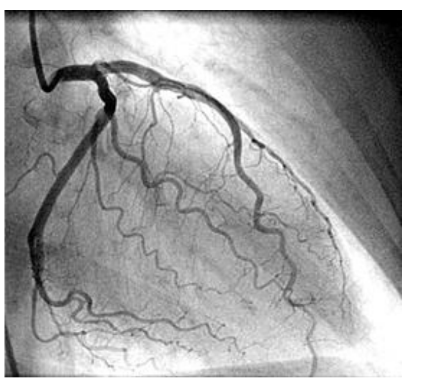

Your doctor (cardiologist) has referred you for a procedure in the cardiac catheterisation lab (cath lab). This is so they can either make a diagnosis or proceed with a treatment. X-rays are often used to allow the consultant to see the equipment being used (such as catheters and leads) and structures in your heart (such as coronary arteries, as seen below).